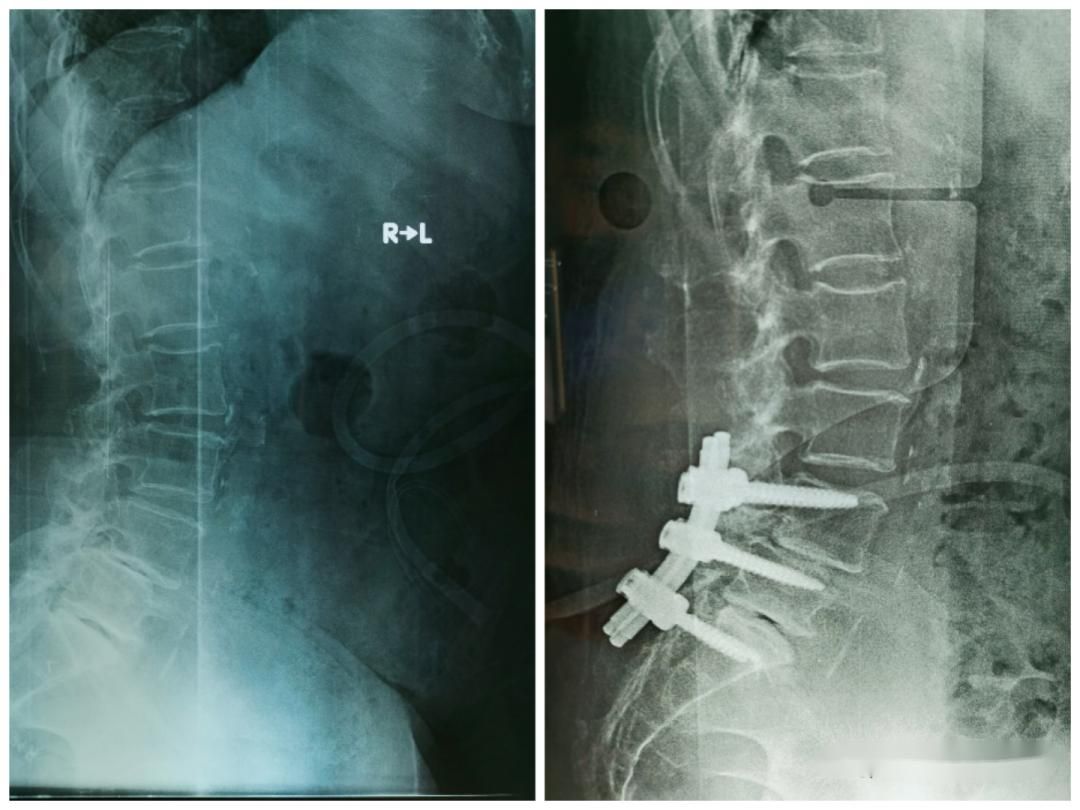

根据侧位X线片对腰椎滑脱的椎体对应其下位椎体滑移的百分比判断严重程度。

Ⅰ度腰椎滑脱<25%;

Ⅱ 度腰椎滑脱个于25%~49%之间;

Ⅲ 度腰椎滑脱在50%~74%之间;

IV 度腰椎滑脱在75%~99%;

Ⅴ 度腰椎滑脱,指椎体滑移至下一椎体水平以下,即所谓完全滑脱。

行腰椎X线检查,可见相邻两椎体之间的腰椎移位

对于经保守治疗无效,或者X线提示,Ⅲ度以上的严重腰椎滑脱导致肢体运动障碍者,应行手术治疗。

应根据临床表现和影像学资料选择合适的术式